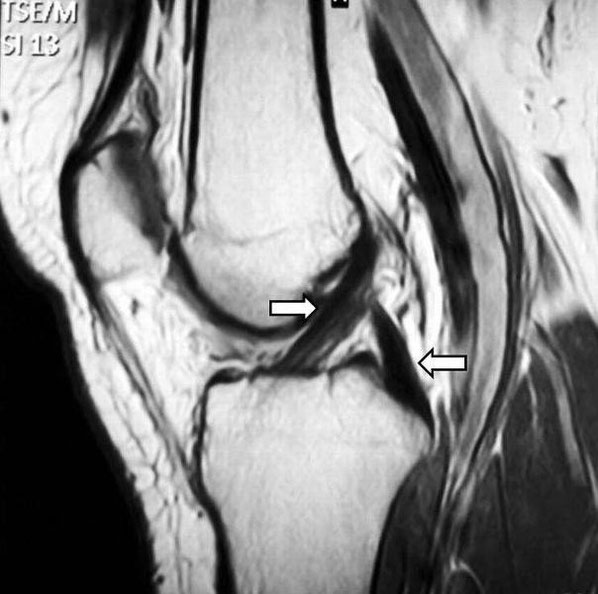

Um den genauen Schaden zu beurteilen, wird üblicherweise eine Magnetresonanztomographie (MRT) durchgeführt, die Aufschluss über den Grad der Kreuzbandverletzung und mögliche Begleitverletzungen, wie Meniskus- Innenband- und Knorpelschänden, gibt. Zusätzlich kann eine Ultraschalluntersuchung zum Ausschluss anderer Verletzungen beitragen.